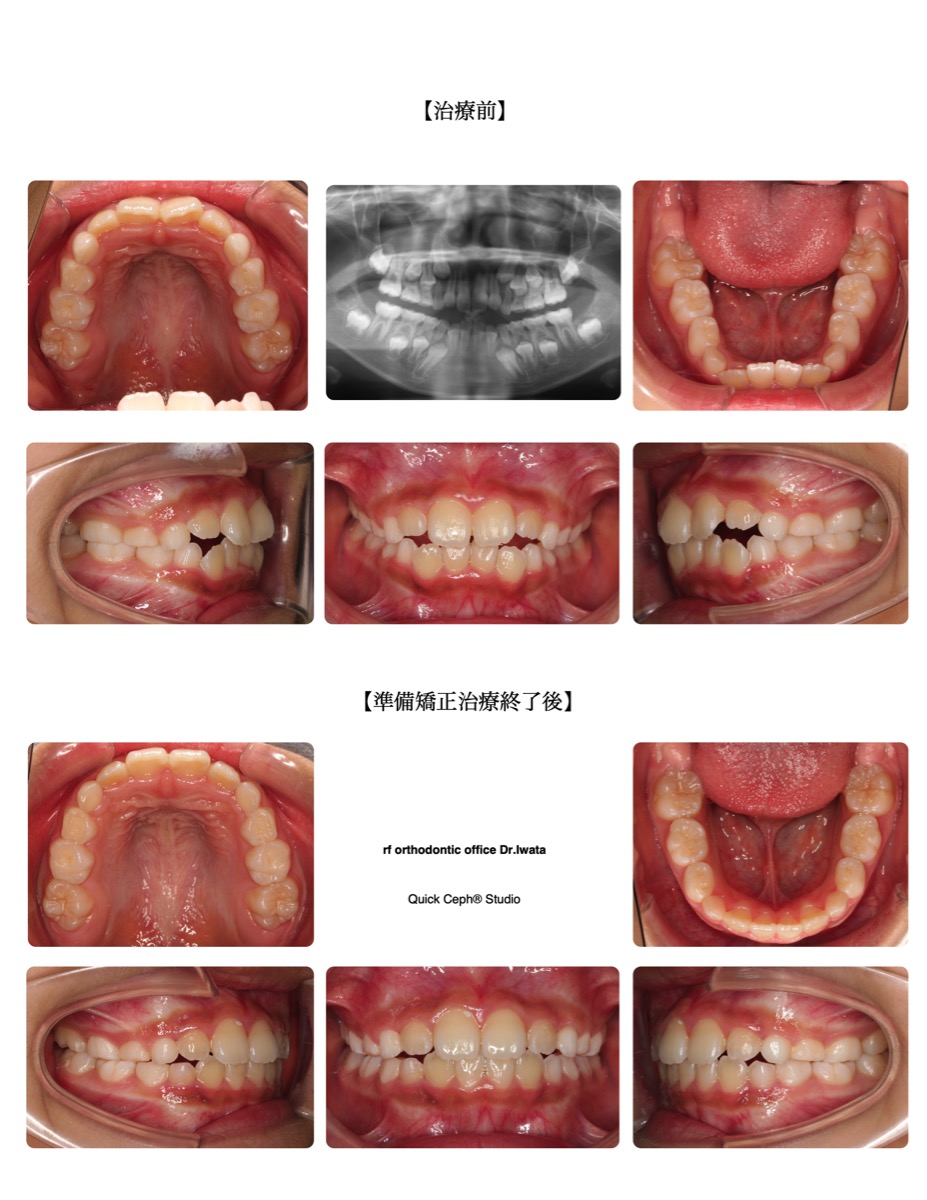

【主訴】かみ合わせが深く、上の前歯が変な向きで生えてきた。下の乳犬歯も結構前に抜けたが永久歯がなかなか生えて…